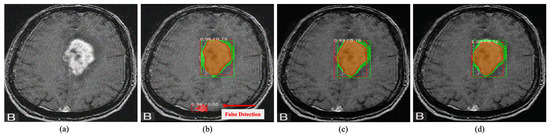

Qualitative evaluation plays an important role in medical image analysis [1,64]. Therefore, this study focused on qualitative comparison along with quantitative comparisons. Figure 5, Figure 6 and Figure 7 illustrates the visual comparison between the proposed method and existing MID methods.

As can be seen, the proposed method is proficient in improving the perceptual quality of degraded noisy images dramatically. It can remove a substantial amount of noise while maintaining the details of a degraded input image. Most notably, the method shows its consistency over the existing MID techniques in all image categories without producing any visually disturbing artefacts.

Figure 5. Qualitative comparison of radiology image denoising at σ = 50 . The proposed method illustrates significant improvement over the existing denoising method by improving perceptual image quality. (a) Noisy input. (b) Result obtained by BM3D [11]. (c) Result obtained by DnCNN [16]. (d) Result obtained by Residual MID [12]. (e) Result obtained by DRAN (proposed). (f) Reference sharp image. Source by: (https://www.kaggle.com/mateuszbuda/lgg-mri-segmentation).